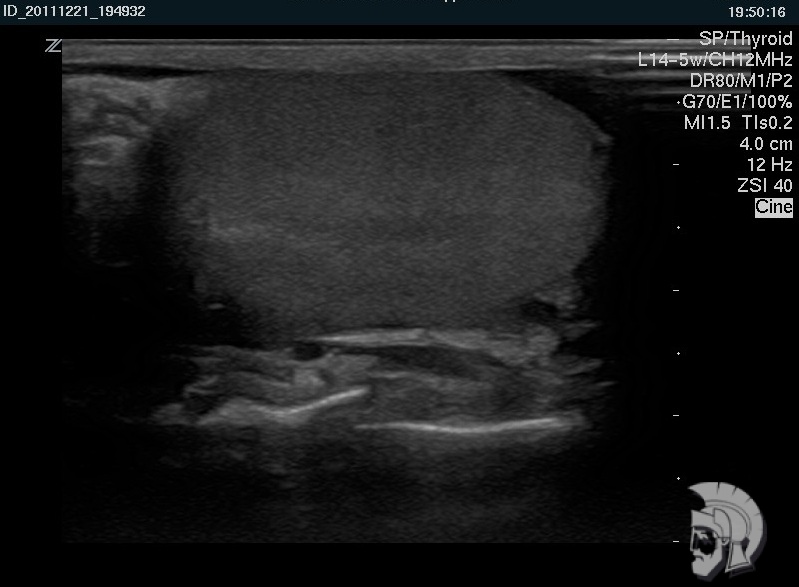

Резкая боль в паху заставила обратиться к врачу. После диагностики на специальном аппарате УЗИ было назначено скорое лечение. Спасибо за быструю диагностику и лечение! Очень тактичный и профессиональны й персонал! С ув. Михаил Васильевич, г.Пятигорск.